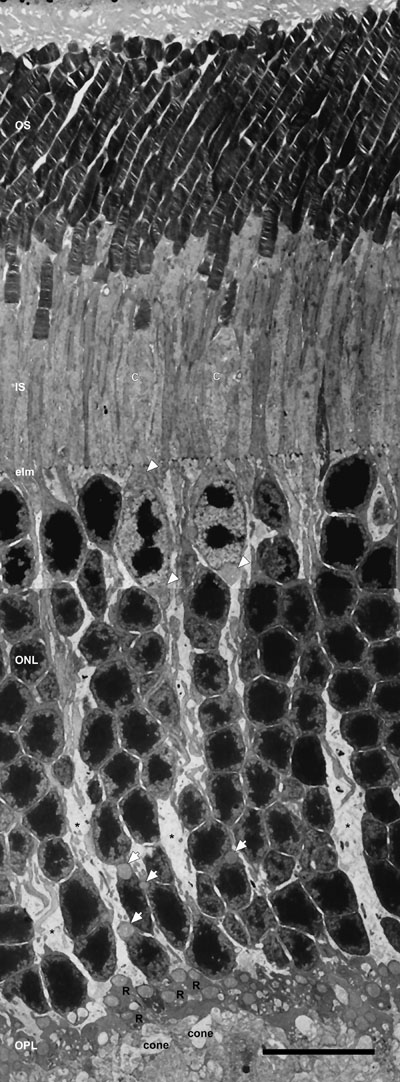

Figure 4. Low-magnification electron micrograph of longitudinal section of the entire photoreceptor layer

Rod and cone (C) photoreceptors are distinguished by several morphological differences. Rod inner segments (IS) are longer, thicker and located more distally in the retina, whereas cone IS are larger and more electron lucent. The cone nuclei are located in the outer third of the outer nuclear layer (ONL), contain several clumps of irregularly shaped heterochromatin and possess two juxtanuclear mitochondria: one above and one below the nucleus (black outlined white arrowheads). The large mitochondrion at the base of the cone nuclei is located at the origin of the wide cone axon, as previously noted [53]. Rod nuclei are present throughout the ONL and contain a single compact mass of heterochromatin. Single juxtanuclear mitochondria are present in many rod somas located in the inner third of the ONL (black outlined white arrows). Numerous synaptic terminals, with large mitochondria, are in the outer plexiform (OPL). Three to five tiers of dark-staining rod spherules (R) overly a single row of more electron lucent cone pedicles (cone) that contain multiple mitochondria. Müller glial cell processes extend throughout the OPL and ONL, and terminate at the external limiting membrane (elm). Scale bar equal 10 μm.